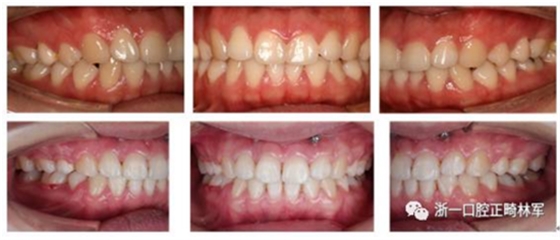

我們給她拔了4顆牙第一前磨牙,打了骨釘,來排齊牙齒,內(nèi)收前牙,改善側(cè)貌,后期又做了牙齦小手術(shù),幫她把露齦笑也解決了,最后治療結(jié)束時她不僅牙齒整齊、咬合良好,而且側(cè)貌漂亮,治療前嘴巴前突、下巴后縮、露齦笑的問題都改善了,她對此很滿意。一起來看看效果吧!

治療前后面像、口內(nèi)像對比